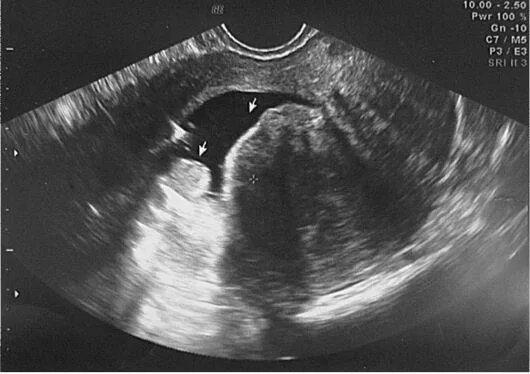

Серозометры в матке что это такое